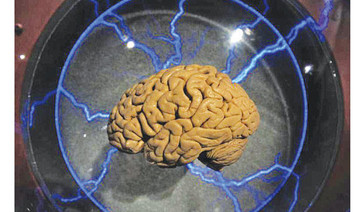

Neuralink is developing a brain implant it hopes will help paralyzed people walk again and cure other neurological ailments.

- Neuralink is developing a brain implant it hopes will help paralyzed people walk again and cure other neurological ailments